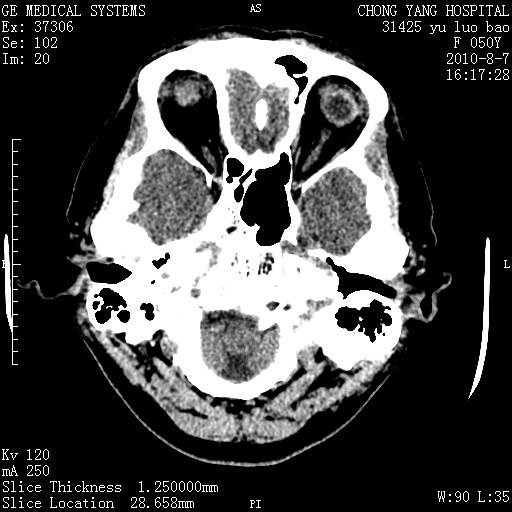

标题: CT28285:听力下降一年,头昏。 [打印本页]

标题: CT28285:听力下降一年,头昏。

右侧桥小脑角区占位--听神经瘤,建议增强或mri检查。

右侧桥小脑角去等密度占位,右侧内听道扩大、骨质吸收,考虑:右侧听神经瘤,建议增强检查。

右侧内听道扩大、骨质吸收,中脑受压左移,考虑:右侧听神经瘤,建议增强检查。支持!

右侧桥小脑角区等密度占位,内耳道扩大,听神经瘤